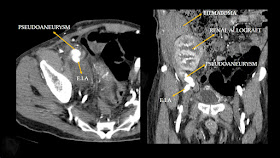

Large external iliac artery pseudoaneurysm : vascular complication of renal transplantation